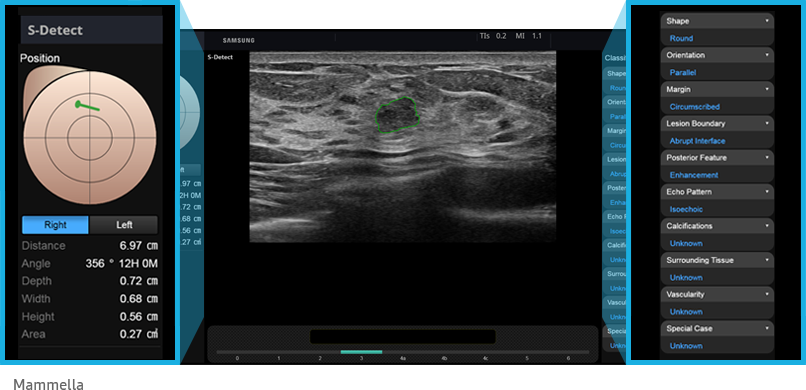

Le innovative tecnologie proprietarie di Samsung supportano la diagnosi assicurando un maggiore dettaglio e velocizzano i flussi di lavoro.